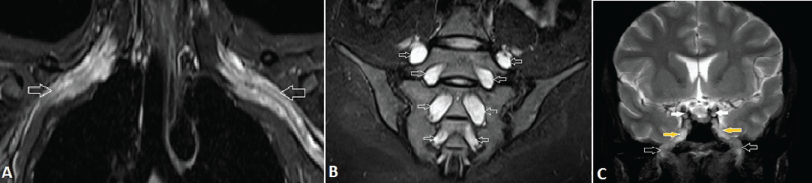

| Figure 12: A 29-year-old female with chronic inflammatory demyelinating polyneuropathy (CIDP). A, Coronal fat-suppressed T2-weighted MR image shows bilateral symmetrically enlarged and hyperintense BP (arrows). B, Coronal fat-suppressed T2-weighted MR image shows diffuse marked symmetrical hypertrophy and abnormal high signal of the lumbosacral nerve roots (arrows). C, Coronal T2-weighted MR image of brain shows marked thickening of the cranial nerves in the lateral wall of cavernous sinus and foramen ovale. Note the enlarged oculomotor nerves (white arrows) and mandibular nerves (black arrows), coming out from Meckel’s cave (yellow arrows) into the masticator space through the enlarged foramen ovale. | ||